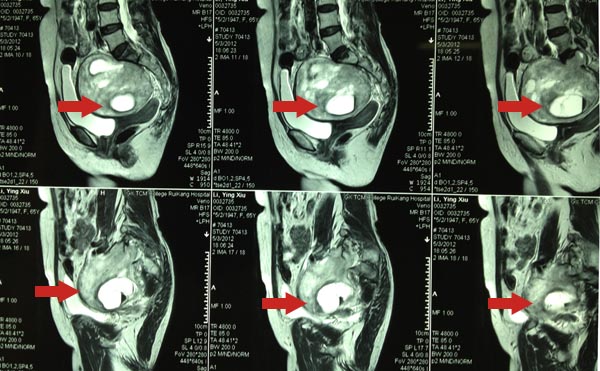

骨脊柱一区陈远明主任,陈锋主任,周先明及黄民锋副主任详细了解患者病情后,结合本院的盆腔MRI增强及盆腔彩超提示:盆腔内肿物混合性回声,肿物约11×9×10cm大小,考虑神经源性肿瘤?,另胃肠外科、肿瘤科、妇科等科室会诊后都建议尽快手术治疗,了解肿物性质。陈远明主任集中科室成员意见后,考虑该肿物为神经源性,首先考虑脊索瘤,该瘤好发于颅底及骶尾部,为低度恶性的肿瘤,切除后易复发,一般术后需放疗;畸胎瘤也不能排除,该瘤中可能出血头发、骨组织等;还有可是罕见的巨大神经鞘瘤,该瘤属于良性。结合患者目前身体状况,认为肿物过大与周围组织粘连,重要血管分布集中,肿物蒂部血管丰富,术中出血量多,采用前路经腹膜外切口切除肿物。陈远明主任及周先明副主任亲自主刀,手术过程顺利,肿瘤重量约1000g左右。

治疗前CT片